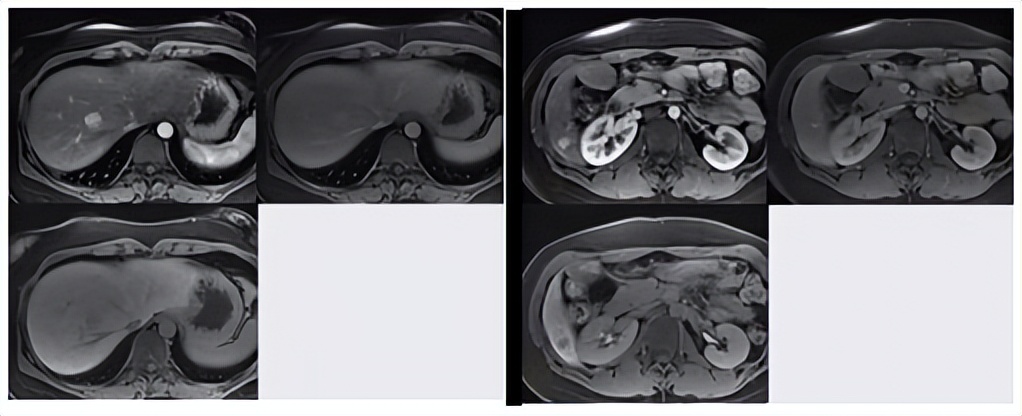

影像(图13-14):MRI,动脉期均匀显著强化,门脉期稍强化,肝胆期为低密度,符合腺瘤影像学改变。

图13-14